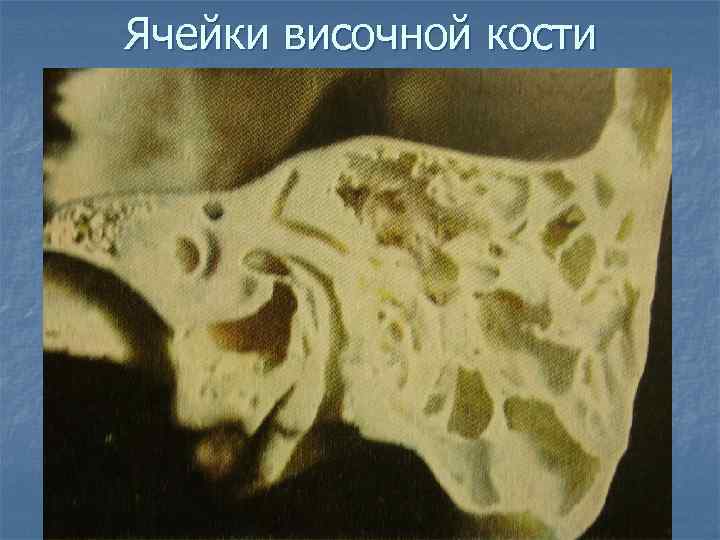

КТ анатомия сосцевидного отростка: особенности и показания